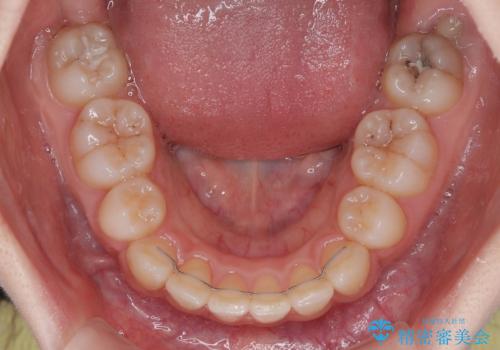

抜歯矯正により、下唇が前方に突出した感覚が大幅に改善されました。